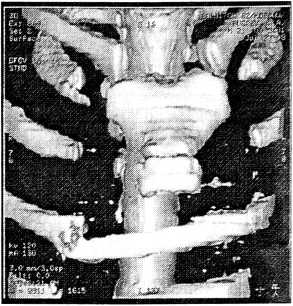

Больной повернут на левый бок. На правой боковой поверхности грудной стенки выкроен кожно-мышечно-костный лоскут из широчайшей мышцы спины с кожей и фрагментами ІХ-ХІ ребер. Кожная часть лоскута соответствовала по размерам образовавшемуся после удаления опухоли дефекту, ребра были включены в лоскут следующим образом: срединный фрагмент взят полностью, а два соседних расщеплены вдоль и использованы только их наружные половины. Лоскут развернут на сосудистой ножке и проведен через подкожный тоннель в зону дефекта на передней поверхности грудной стенки. Три фрагмента ребер фиксированы толстой синтетической нитью к оставшимся концам ІII-ІѴ ребер для восстановления каркасной функции грудной клетки. Мышечной частью укрыты перемещенные костные фрагменты и места соединения ребер. Кожным лоскутом полностью закрыт дефект мягких тканей (рис. 4. 5).

Рис. 5. Трехмерная компьютерная реконструкция послеоперационного дефекта грудины и ребер. Видно верхнее перемещенное ребро, перекрывающее дефект грудины.